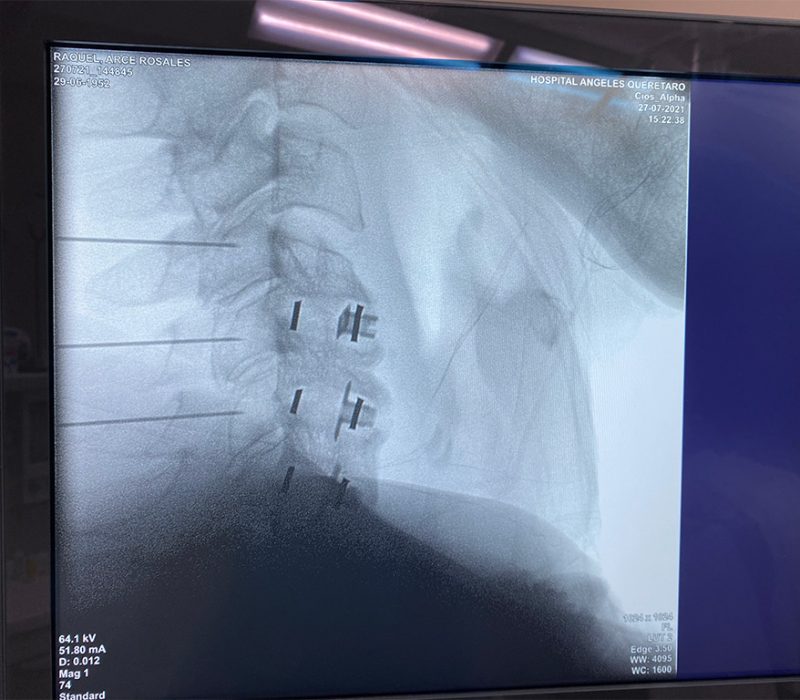

Un bloqueo es una inyección dirigida a un músculo, nervio o articulación de un anestésico local acompañado de un antinflamatorio, se basa en la interrupción de la nocicepción o de la señal dolorosa, en otras palabras se trata de «apagar» el dolor. Puede ser temporal y reversible por lo que en ocasiones le llamamos bloqueos diagnóstico, pues al aislar una estructura dolorosa podemos identificar de forma más específica el origen del dolor y posteriormente ofrecer técnicas con mayor durabilidad.

Estos procedimientos se deben realizar siempre bajo guía fluoroscópica y/o con guia de ultrasonido, esto permite obtener imágenes en tiempo real de las estructuras internas con lo que el procedimiento tiene mayores índices de eficacia al estar seguros que el medicamento esta siendo depositado en la estructura deseada y ofrece mayor seguridad para el paciente.